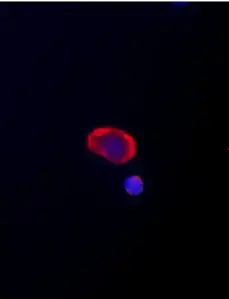

Example images from patient blood samples

Examples of Portrait+ CTC staining kit samples